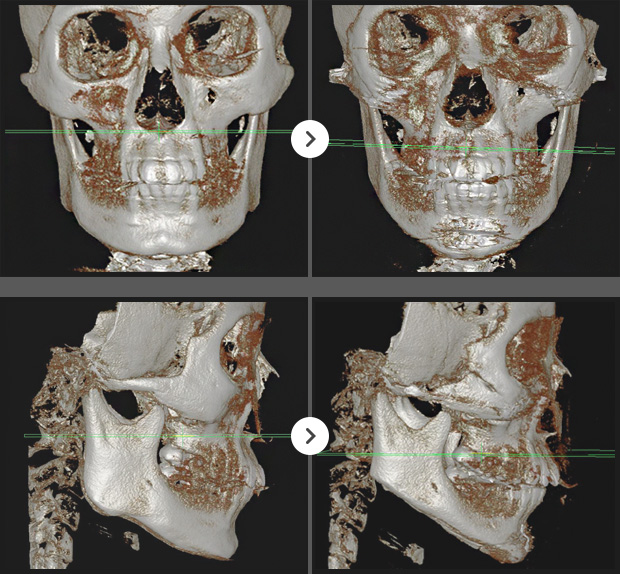

CT BEFORE & AFTER

3D광대, 긴곡선사각턱, 앞턱V절골(3mm전진)

긴곡선사각턱,앞턱V절골(길이축소)